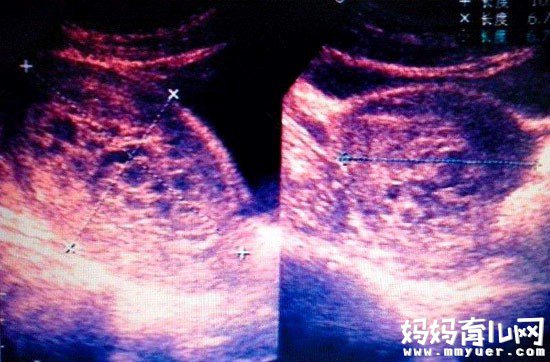

说到葡萄胎,相信大家一定不陌生。葡萄胎是一种异常怀孕状态。又称为水泡状胎块。葡萄胎因妊娠后胎盘绒毛滋养细胞增生、间质水肿,而形成大小不一的水泡,水泡间借蒂相连成串,形如葡萄而得名。葡萄胎可以分为两种,一种是完全性葡萄胎,一种是部分性葡萄胎。完全性葡萄胎是指受精卵完全没有发育成胚胎;部分性葡萄胎是指受精卵因为发育不正常而无法存活。无论是哪一种葡萄胎,都是不正常的,需要进行流产。

正常怀孕中,受精卵从爸爸和妈妈那里各获得23条染色体。在大多数完全性葡萄胎病例中,受精卵没有从妈妈那里获得染色体,可是从爸爸精子中获得的染色体被复制了,那么结果是受精卵从爸爸那里获得了2组同样的染色体,而从妈妈那里没有获得任何染色体。在这种情况下,就不会形成胚胎、羊膜囊或任何正常的胎盘组织,相反,胎盘组织形成了一堆水泡,样子看起来就像一串葡萄。

在大多数部分性葡萄胎病例中,受精卵从妈妈那里获得了一套正常的染色体,但是从爸爸那里获得的染色体数量加倍了,结果是受精卵中含有69条染色体,而不是正常的46条。如果从精子中获得的染色体被复制了,或者是有2个精子与同一枚卵子结合,都会出现这种现象。在这种情况下,在成葡萄串状的异常组织中,还有一些正常的胎盘组织。受精卵确实会开始发育成胚胎,所以,可能会形成胎儿,或是一些胎儿组织,也许会有羊膜囊。但是,即使有胎儿形成,大多数情况下,它也不够正常,没有办法存活。